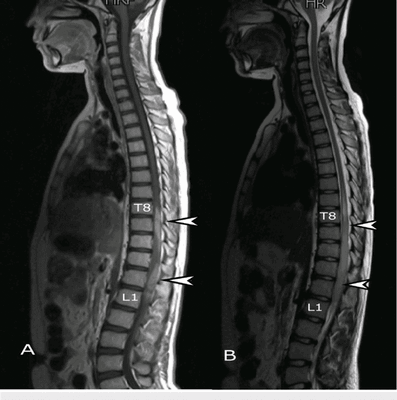

Поскольку для хорошей визуализации магнитно-резонансному томографу нужно много клеток с атомами водорода, то ткани с большим содержанием воды лучше всего визуализируются на МРТ снимках. Поэтому МР-томография позвоночника очень хорошо показывает:

- спинной мозг;

- нервные волокна;

- сосудистое русло;

- мягкие ткани (мышцы, сухожилия, связки, межпозвоночные диски).

С ее помощью врачи могут выявлять:

- все патологии мозговых оболочек каналов и вещества мозга;

- грыжи, протрузии, стеноз, спондилез;

- дегенеративные изменения в хрящевых структурах (например, остеохондроз);

- опухоли мягких тканей.

МРТ позвоночника дает возможность хорошо визуализировать спинной мозг, мягкие ткани, грыжу межпозвоночного диска. В случаях, когда неврологам, травматологам и хирургам необходимо получить трёхмерную реконструкцию и исследовать кости позвоночника в разных плоскостях или диагностировать обызвествление межпозвоночного диска, применяется КТ позвоночника.